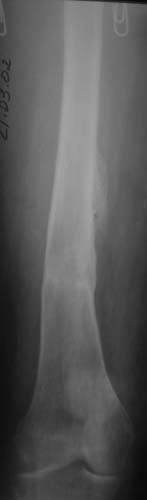

Уважаемые коллеги!Женщина, 35 летВ прошлом по поводу врожденного вывиха бедра перенесла операцию остеотомии по Шанцу

с удлинением правой ноги за счет бедра на уровне диафиза. В последнее время прогрессируют боли в правом тазобедренном суставе, порочное положение правой ноги, затруднена ходьба.Вопросы:1) Целесообразно ли эндопротезирование правого тазобедренного сустава?2) Целесообразный ли следующие действия: канал бедренной кости предполагаем вскрыть для введения ножки протеза на высоте угловой деформации, предполагаем низведение большого вертела с мышцами; протез будет подобран индивидуально, предполагается умеренная версия?В приложении рентгенограммы и трехмерная КТ.В цветном и более качественном варианте КТ размещена здесь